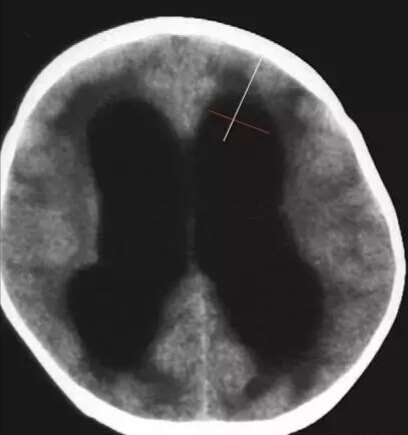

第二招:额角比率-垂直于额角长轴测量额角的最宽部分 脑萎缩-小

脑积水~宽